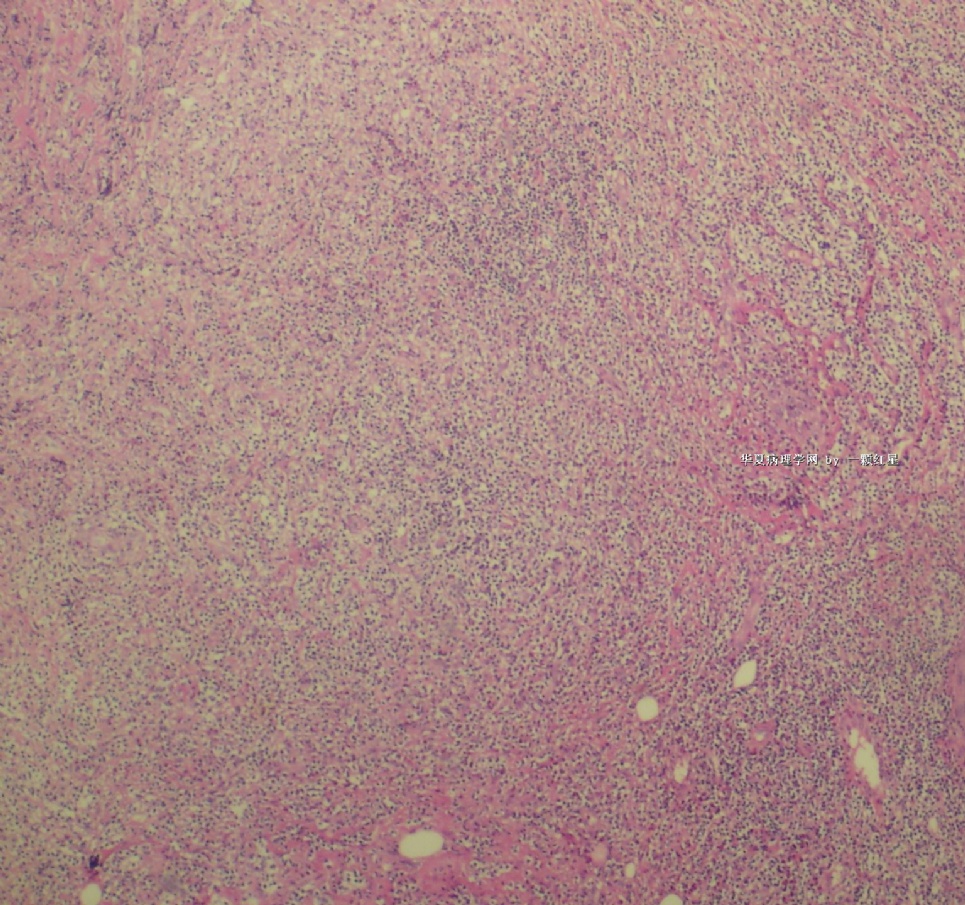

标本名称:  左前臂数个大小不等的皮下肿物。

• 左前臂数个大小不等的皮下肿物     淋巴瘤?图3

图3

病例不错。细胞胞浆透亮,间质血管丰富,图片不是很清晰,似乎有嗜酸粒细胞?

恶性,首先考虑T-NHL。IHC证实。

既往有NHL病史,图片不太清晰,细胞弥漫,胞浆透亮,首先考虑T细胞淋巴瘤。